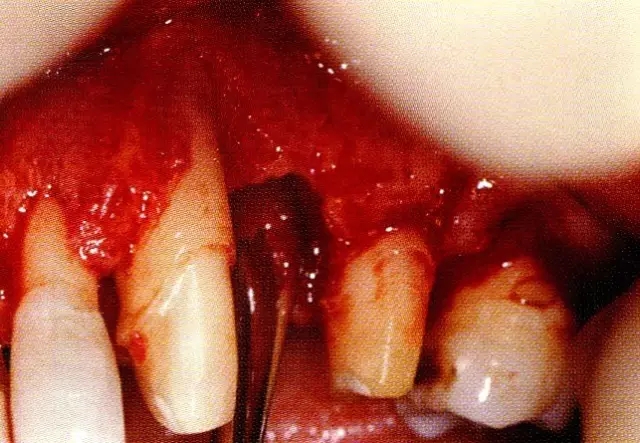

▲圖7-3  將posterior interproximal類型的非吸收性覆膜修整后進(jìn)行垂直懸吊縫合做固定。垂直懸吊縫合后,確定覆膜是否會(huì)動(dòng)搖,再將齦瓣與之緊密縫合。